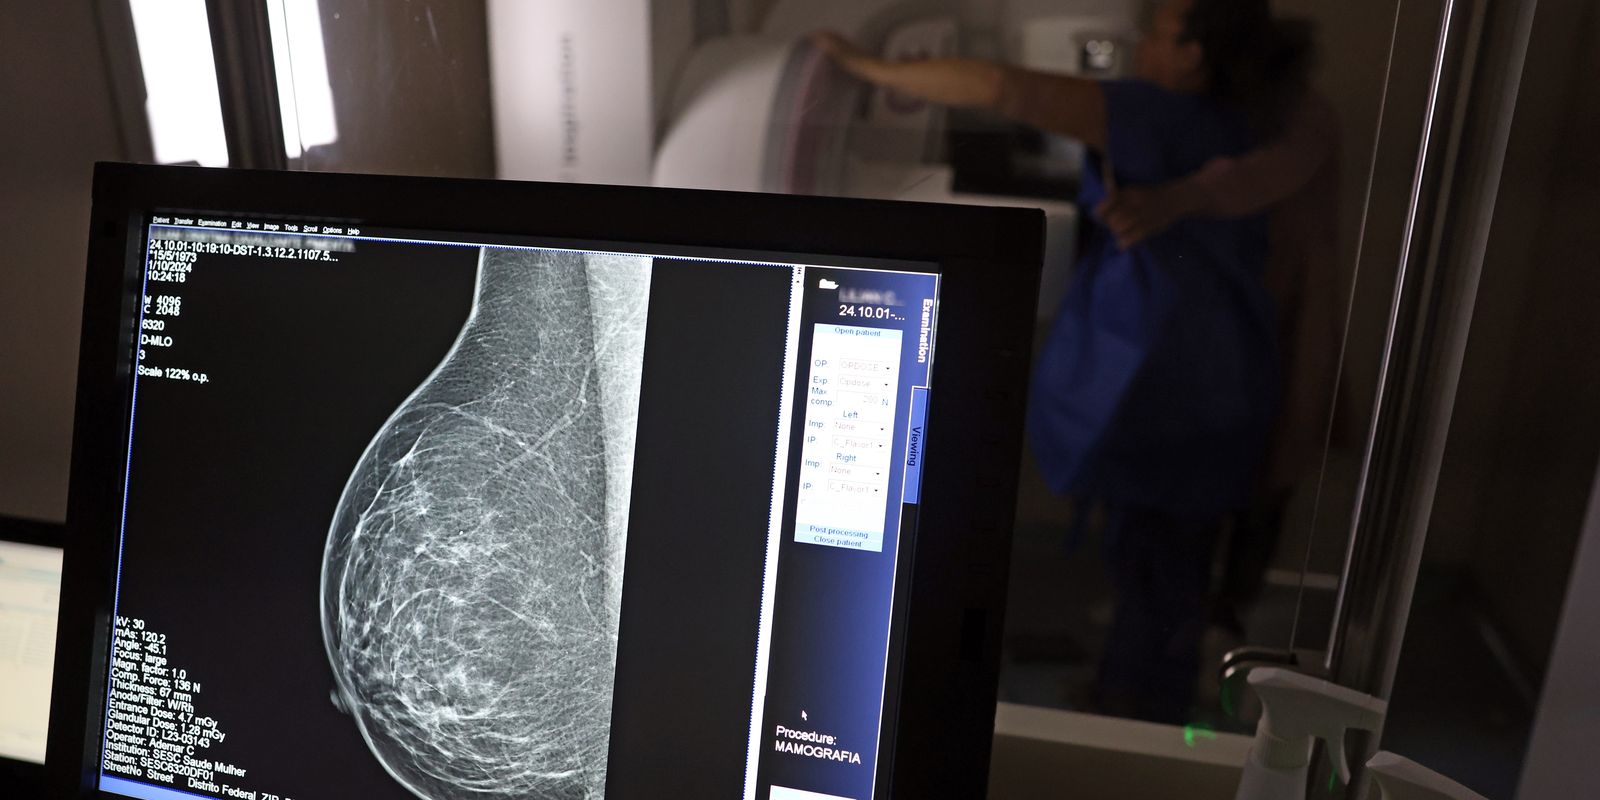

Para a entidade, os números reforçam a importância de ampliar o rastreamento do câncer de mama por meio da realização de mamografia em mulheres abaixo dos 50 anos e acima dos 70 anos, faixas etárias que não estão incluídas na recomendação padrão de exames preventivos no âmbito do Sistema Único de Saúde (SUS).

O levantamento mostra que, entre janeiro de 2018 e dezembro de 2023, o Brasil registrou mais de 319 mil diagnósticos de câncer de mama, sendo 157,4 mil em mulheres de 50 a 69 anos, faixa etária atualmente recomendada para o rastreamento.

Entre mulheres com idade entre 40 e 49 anos, foram registrados 71.204 casos de câncer de mama, enquanto 19.576 mulheres com idade entre 35 e 39 anos também receberam o diagnóstico da doença. Juntas, ambas as ocorrências representam 33% do total de casos diagnosticados no período.

Já entre mulheres acima de 70 anos, foram identificados 53.240 casos de câncer de mama.